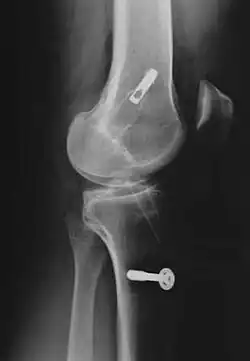

Le décollement ou l'arrachement du LCA de l'os est substantiellement plus rare que la rupture intraligamentaire[5] et n'est pas une rupture de ligament. Ce cas particulier survient plus fréquemment chez les enfants, particulièrement dans le domaine du tubercule intercondylaire du tibia, et possède en général, par refixation de l'arrachement par exemple avec des vis ou des fils métalliques, de bonnes chances de guérison complète.

Pour la reconstruction du LC par transplantation autologue au moyen du tendon patellaire, une partie de celui-ci est prélevée avec des morceaux d'os aux extrémités, technique dite bone tendon bone (os tendon os), ou technique BTB. Il est tiré à travers des canaux élargis (8 à 10 mm de diamètre dans le tibia et le fémur). La longueur de chacun des blocs osseux est de 20 mm. L'ancrage le plus stable de la greffe est obtenu par fixation avec des vis d'interférence. Celui-ci est particulièrement important en vue d'une mobilisation fonctionnelle rapide.